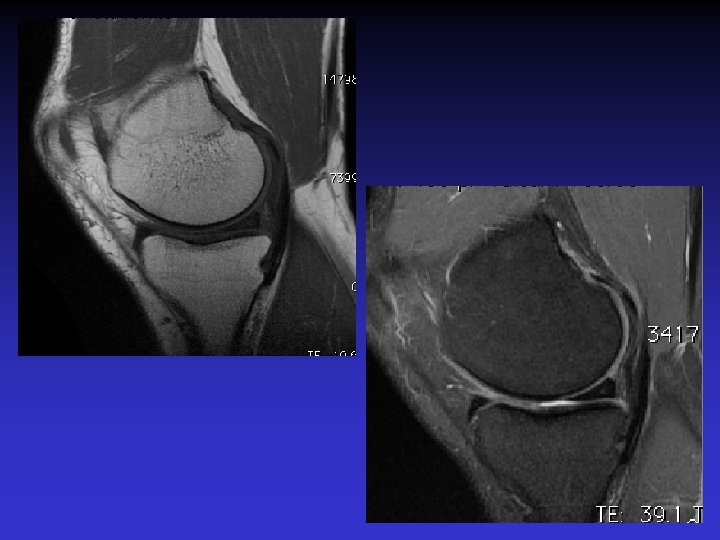

DIAGNOSTIC DIFFERENTIEL • Rupture du LCA • Tumeur synoviale

RUPTURE DU LCA